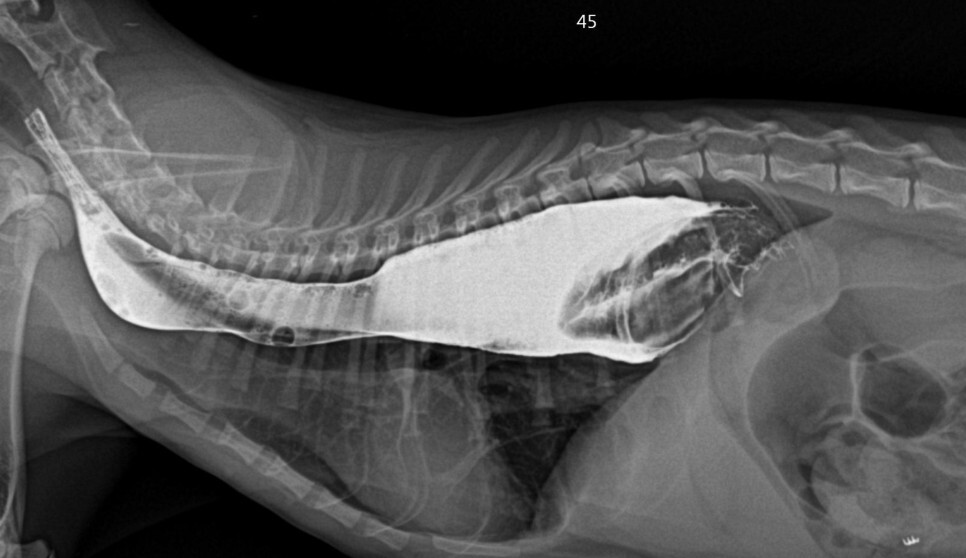

장폐색을 감별하기 위한 조영 촬영에서

내시경 검사와 마찬가지로 확장된 식도와 식도내강으로 돌출된 위 점막을 확인할 수 있었습니다.

장 내 이물이 발견되기는 하지만 개통에는 문제가

없는 것으로 확인되었습니다.